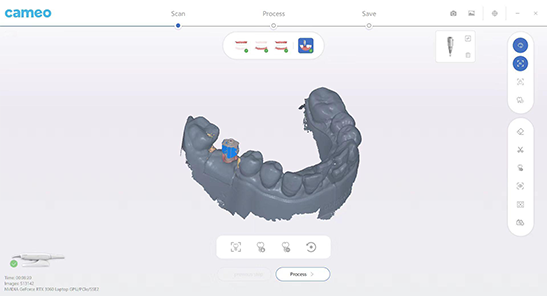

| Implant scan rod matching

The data of planting scanning rod can be imported to realize one-click matching during scanning, improve the accuracy of scanning rod and reduce the rework rate. |